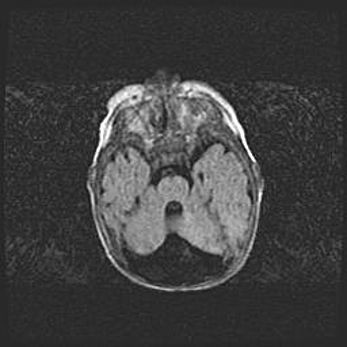

Аномалия Денди-Уокера. Признаки гипоплазии мозолистого тела.

Возраст: 5 месяцев 3 дня

Вес: 5550 г

Пол: мужской

Окружность головы: 39 см

Срок гестации: 40 недель

Аномалия Денди-Уокера – это порок развития головного мозга, для которого характерна триада симптомов: гипотрофия или аплазия червя мозжечка и/или полушарий мозжечка, расширение четвёртого желудочка с формированием ликворной кисты задней черепной ямки, гипертензионная гидроцефалия различной степени.

Гипоплазия мозолистого тела относится к дефектам внутриутробного этапа развития мозговой ткани, возникающим в процессе закладки структур головного мозга, что происходит на начальных этапах развития эмбриона.